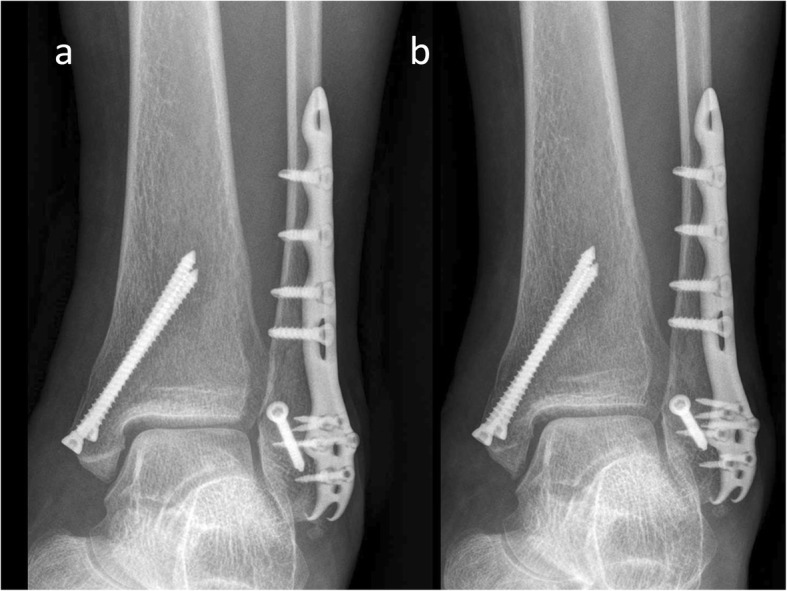

At the end of the 1-year follow-up, the VAS score, FAOSs, and radiological outcomes (Figs. 2 and 3) of each patient were compared and analyzed with those recorded immediately postoperatively.

Fig. 2.

A 64-year-old woman treated using an interfragmentary screw and an Aplus PLP. a The fracture was well-reduced (immediately postoperative radiograph). b It was united without shortening, further displacement, or changes in OA grade